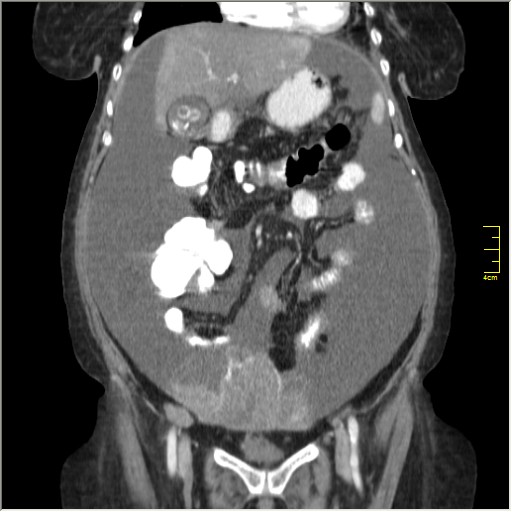

Женщина 72 года. Поступила с жалобами на вздутие живота. После осмотра хирургом, была сразу направлена на КТ брюшной полости.

Как мнение начинающего в КТ: на мой взгляд на серии томограмм определяется обьёмное образование органов малого таза, если так то - лапароскопия.

Итак, асцит с объёмным образованием таза. В данном случае можно быть более конкретным, у пациентки неоплазия правого яичника с региональной лимфаденопатией (увидели?) и выраженным асцитом, характерным именно для злокачественных опухолей яичников. Пациентка оперирована ( операция Вертгейма); диагноз верифицирован: аденокарцинома правого яичника (серозная). Направлена к онкологу для дальнейшего лечения.